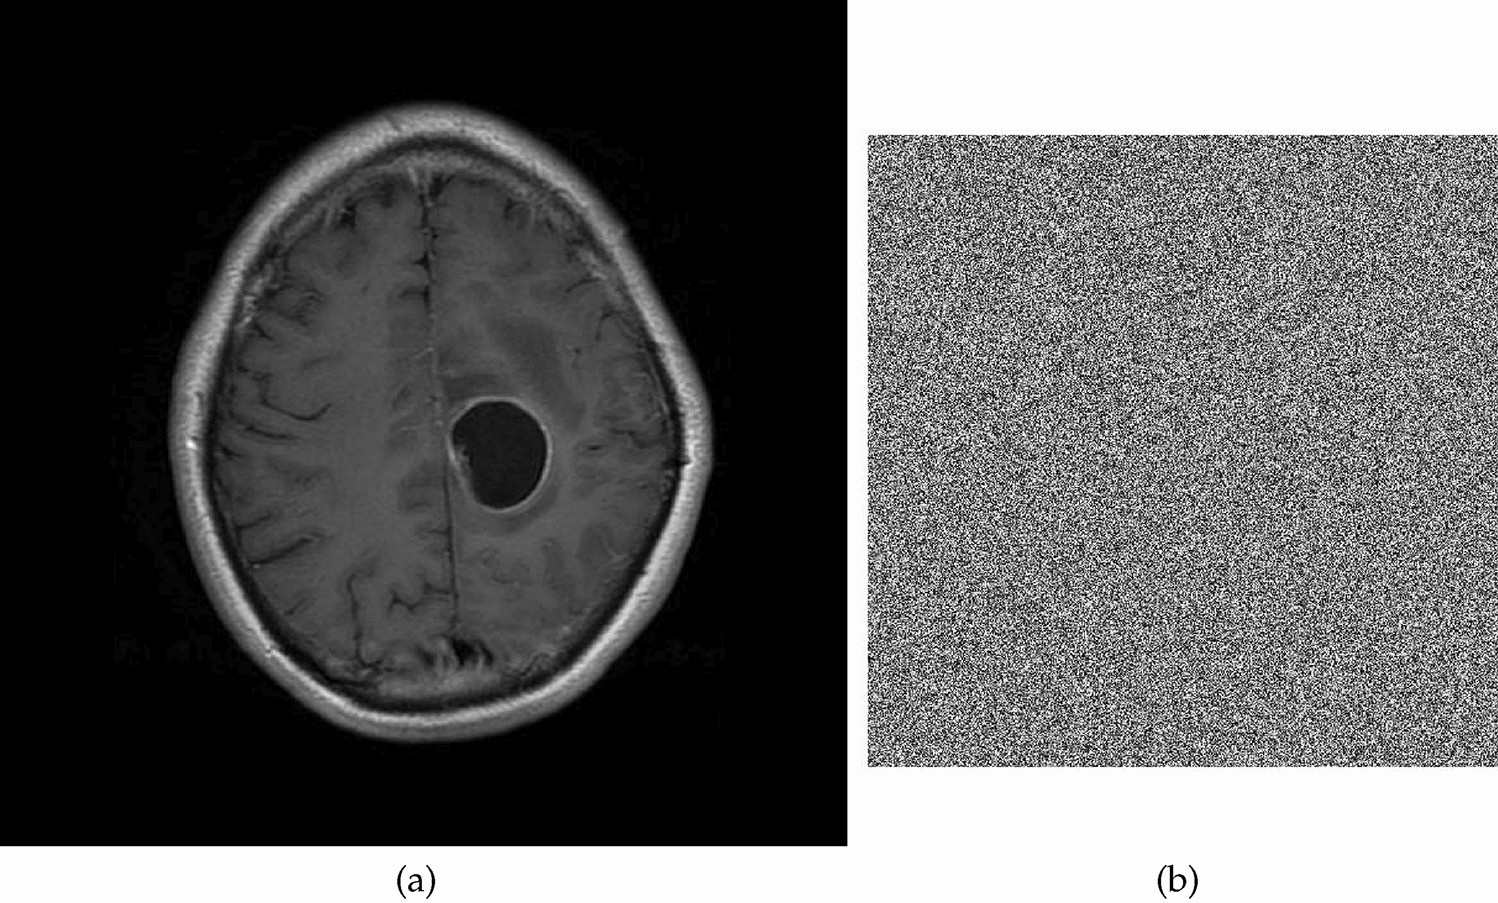

Fig. 7 | Scientific Reports